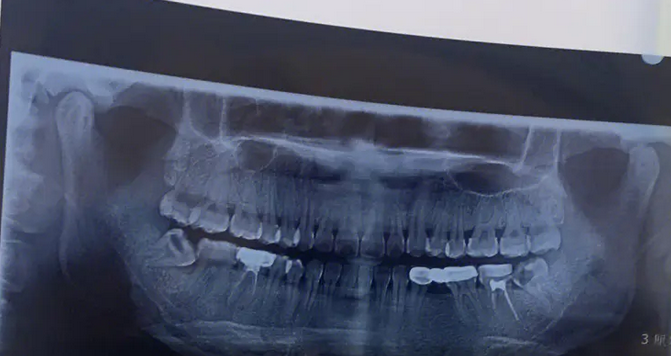

拔智齒之前:

原來我經(jīng)常受到智齒疼痛問題的困擾,為了能夠把智齒拔掉,我在中山大學腫瘤防治中心的口腔科做了拔智齒的手術。拔牙前醫(yī)生給我做了檢查,確定了牙齒狀態(tài)。

image.png